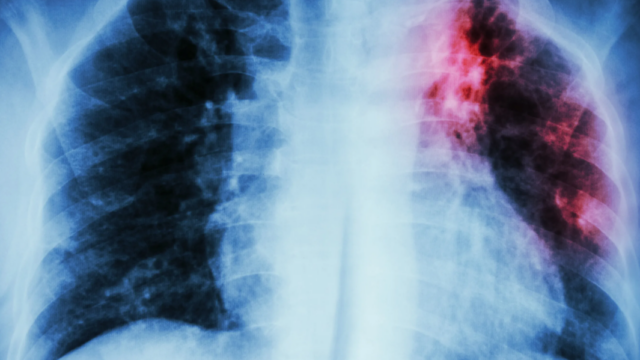

В Краснодарском крае выросло число случае заболевания туберкулезом

В Краснодарском крае зафиксировали рост заболеваемости туберкулезом в 2024 году. Об этом сообщает «Ъ-Кубань» со ссылкой на региональное министерство здравоохранения. В настоящее время более 2500 жителей края получают лечение от активной формы туберкулеза в стационарах и амбулаториях. Пациенты, прошедшие лечение, находятся под пристальным наблюдением фтизиатров в противотуберкулезных диспансерах по месту жительства.